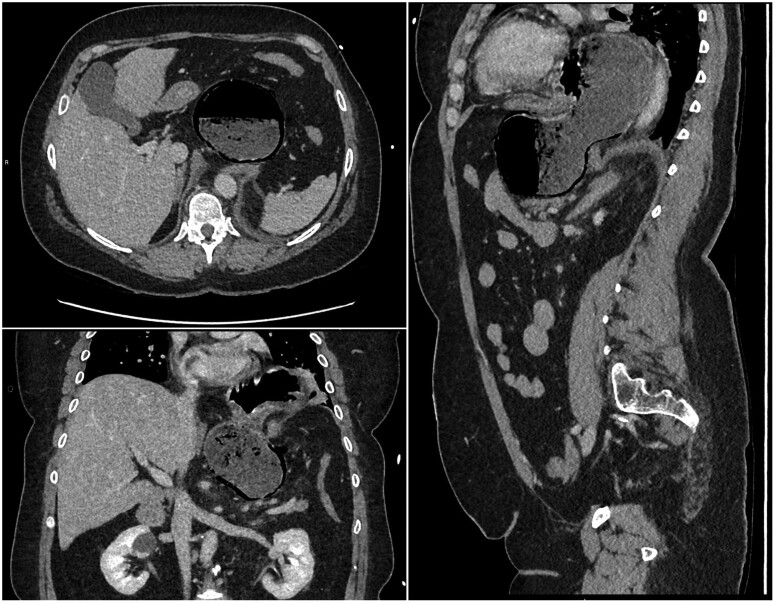

Gastric pneumatosis is a rare finding, and clinicians, when under pressure, find it challenging to immediately identify the cause and decide if the patient requires emergency surgery. We present a case where an initial CT scan demonstrated gastric pneumatosis involving only the greater curvature of the antrum caused by a strangulated hiatus hernia and malrotation of the distal stomach. The CT features suggested the patient required immediate surgery; however, a conservative approach was taken, and a follow-up CT scan 4 days after the onset demonstrated complete resolution and no long-term complications.